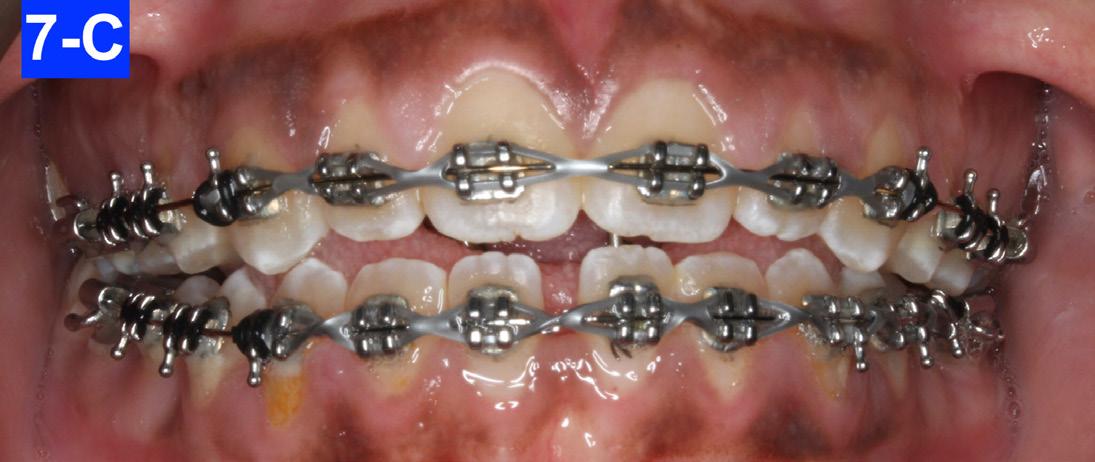

The following appointment, we placed a .018 SS in the maxilla and a .018 NiTi in the mandible. An EC was placed from #13(6) to #23(11), and in the mandible from #43(27) to 34(21) to close the spaces (Figure 7-A, B. C).

Fig. 7-C: MX a. 018 SS, MN a .019 NiTi

Fig. 7-B: MX a .018 NiTi, MN a .016 NiTi